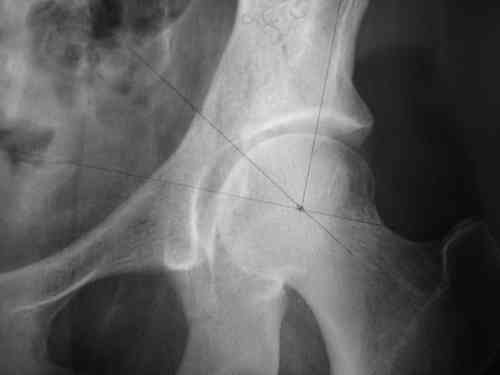

прилагаю пример с такой же давностью травмы, репонировали аппаратом

> в аппарате или одномоментно открыто. Лично я склоняюсь к аппаратному лечению на первом этапе.